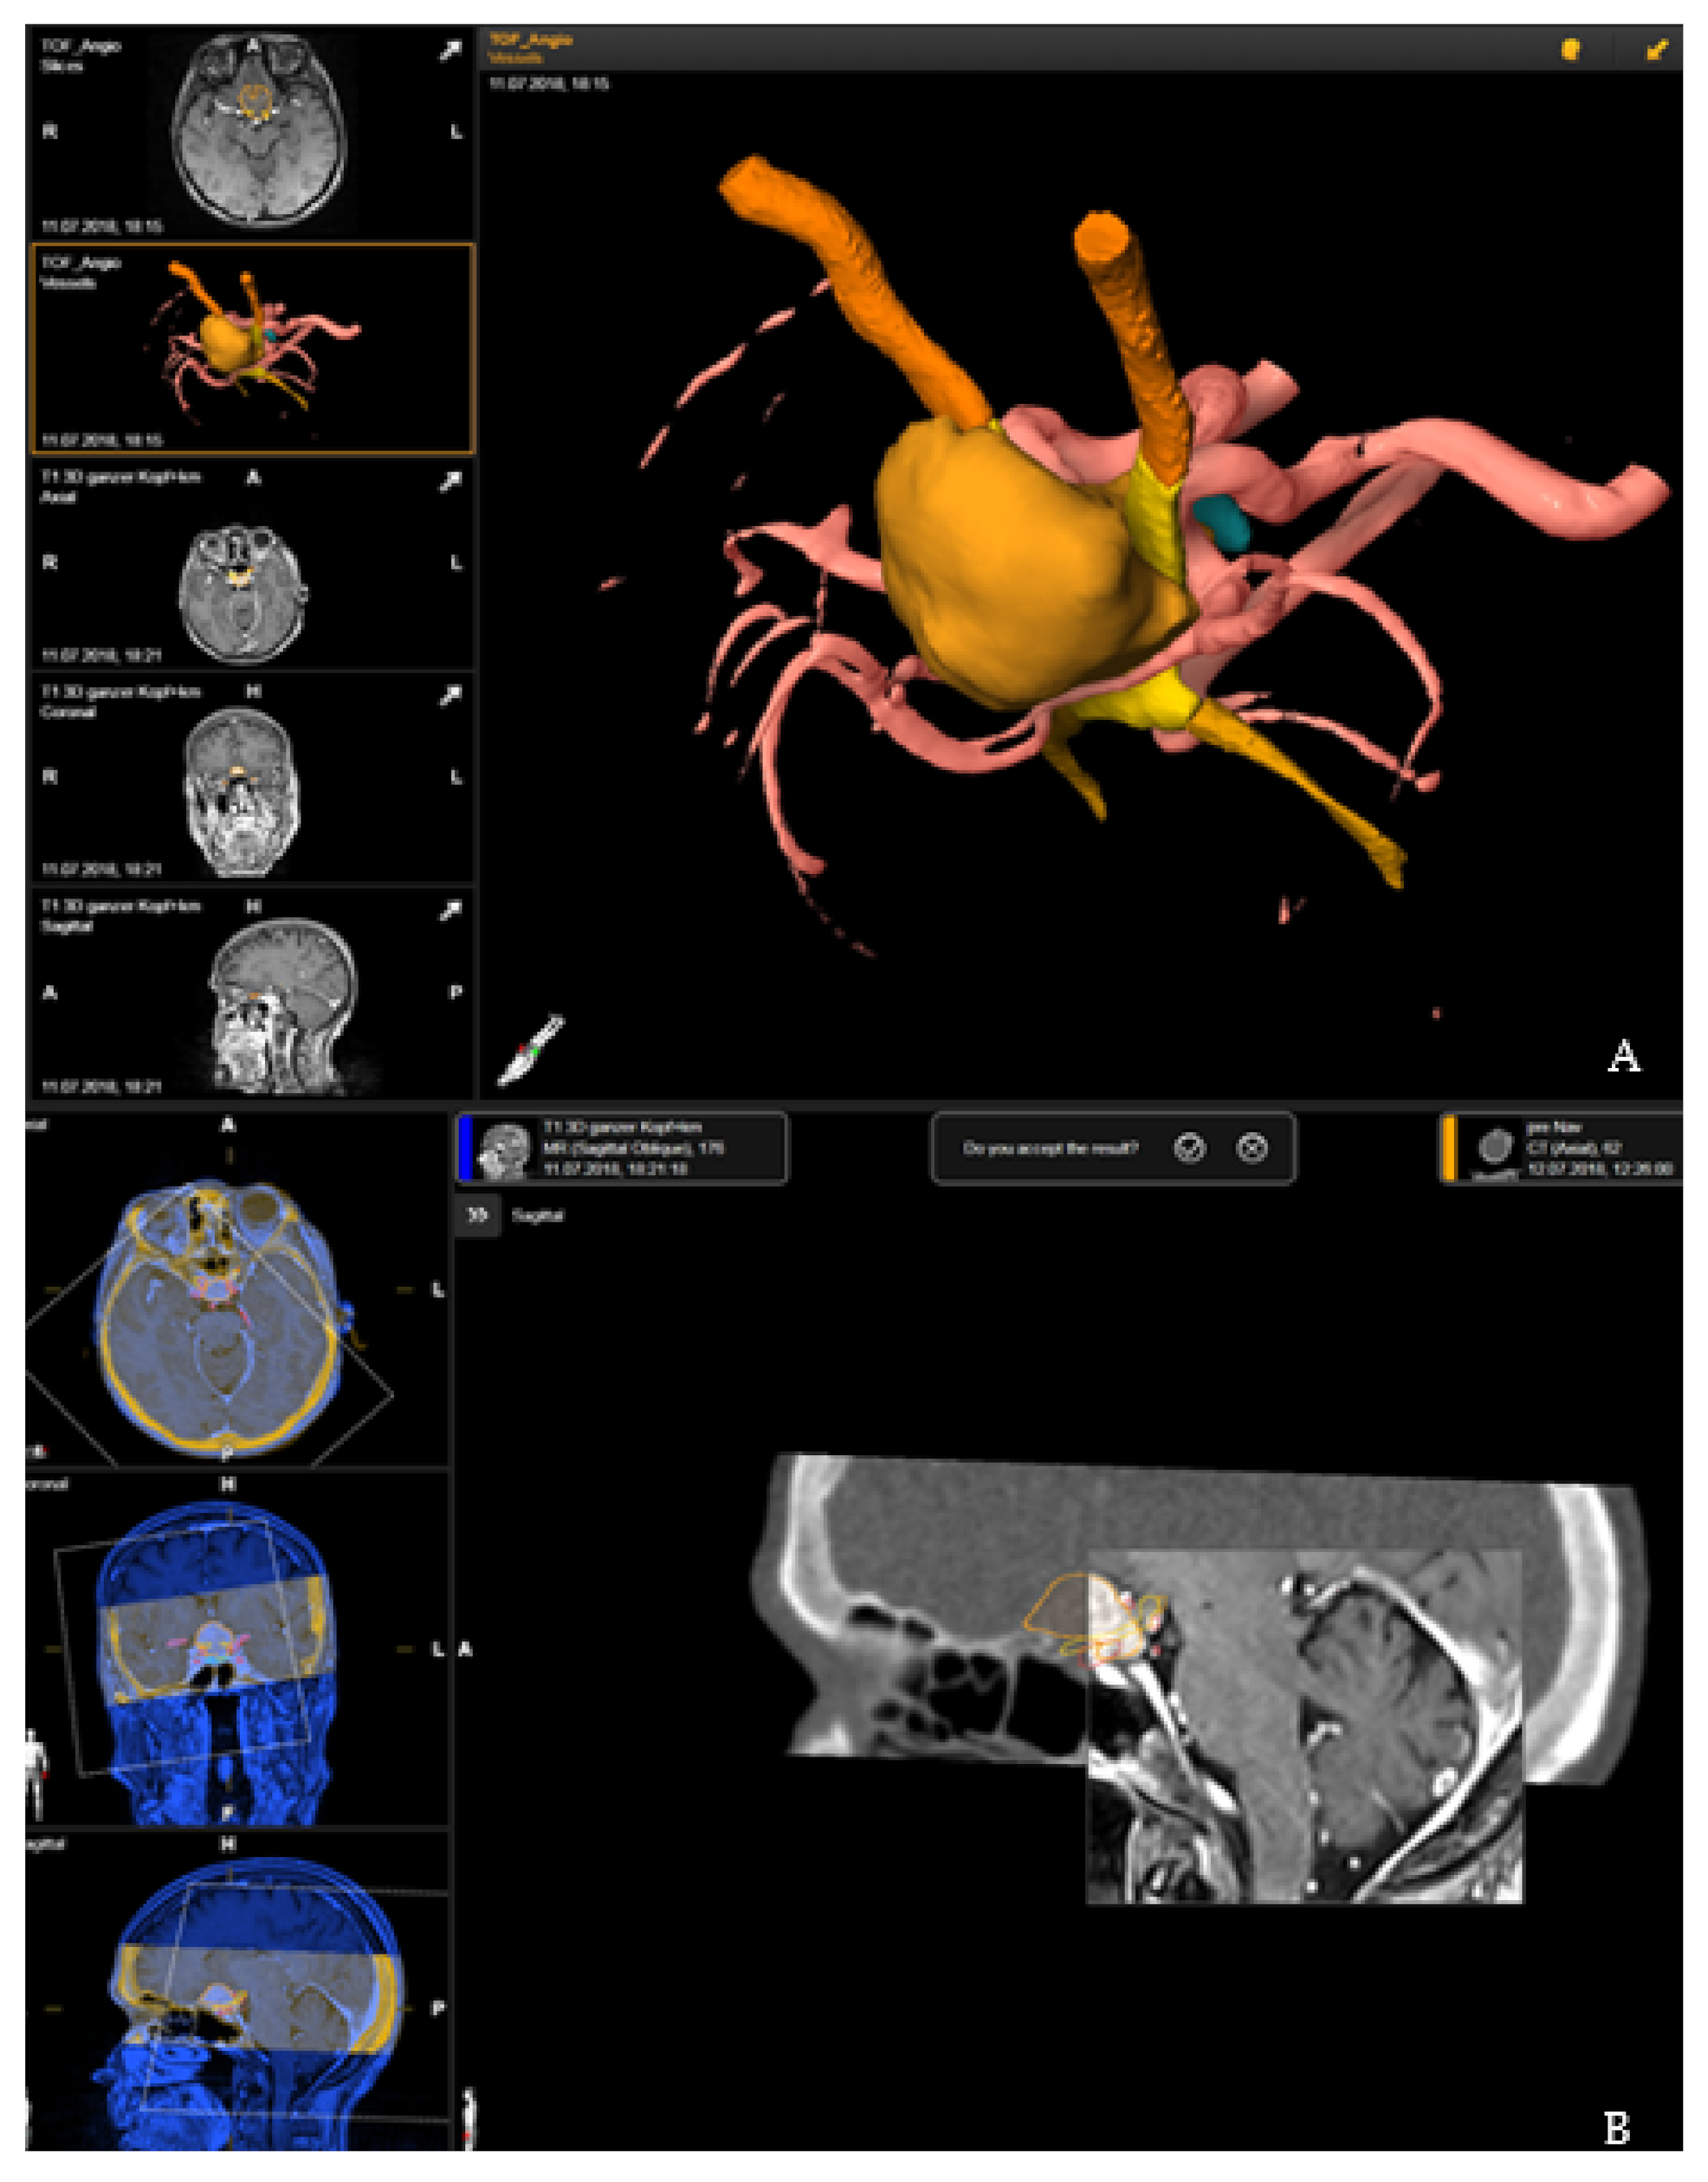

Segmentation of the tumor was usually performed in the T1-weighted post-contrast MRI modality, manually or using autosegmentation with an anatomical mapping element (Brainlab). Brainlab was used to delineate the optic nerves, chiasm, ventricles, pituitary gland or brain stem with unique colors being assigned to each object, and with additional manual segmentation for correction of the automatic segmentation and for segmentation of tumor and risk structures. For segmentation of the vascular risk structures, contrast-enhanced T1-weighted magnetic resonance imaging (MRI), time-of-flight (TOF) MRI angiography or computed tomography (CT) angiography was used and then rigidly registered. Rigid registration was performed by an image fusion element (Brainlab, Munich, Germany). This 3D data set formed the basis for patient registration [7] (Figure 1).

Rigid registration of the preoperative plan with the registration CT scan was performed by image fusion software, Brainlab elements (Brainlab, Munich, Germany). Accuracy of the fusion was checked by a spy-glass feature, with visualization of the preoperative images in an insert of the intraoperative CT, which was moved around for detection of registration failure in all views with appropriate anatomical landmarks (Figure 1).

Case 3: A 67-year-old female patient (patient number 19) with visual deterioration and bitemporal hemianopsia. MRI showed a suprasellar meningioma which was resected via right pterional approach. Figure 7 demonstrates the visualization of the structures in the AR throughout the surgery.

Figure 1. Preoperative planning and image fusion for 67-year-old female patient with suprasellar meningioma (patient no. 19). (A) Visualization of the tumor (ochre), optic nerves and tract (orange) and optic chiasms (yellow) as a 3D object following segmentation in T1-weighted post-contrast magnetic resonance imaging (MRI) and time-of-flight (TOF) MRI angiography. (B) Rigid fusion of computed tomography scan with T1-weighted MRI scan.